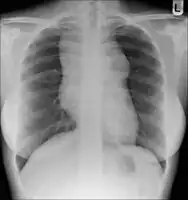

- Lymphadenopathy: the most common symptom of Hodgkin is the painless enlargement of one or more lymph nodes.[14] The nodes may also feel rubbery and swollen when examined. The nodes of the neck and shoulders (cervical and supraclavicular) are most frequently involved (80–90% of the time, on average).[14] The lymph nodes of the chest are often affected, and these may be noticed on a chest radiograph.[14]

After Hodgkin lymphoma is diagnosed, a person will be staged: that is, they will undergo a series of tests and procedures that will determine what areas of the body are affected. These procedures may include documentation of their histology, a physical examination, blood tests, chest X-ray radiographs, computed tomography (CT)/Positron emission tomography (PET)/magnetic resonance imaging (MRI) scans of the chest, abdomen and pelvis, and usually a bone marrow biopsy. Positron emission tomography (PET) scan is now used instead of the gallium scan for staging. On the PET scan, sites involved with lymphoma light up very brightly enabling accurate and reproducible imaging.[29] In the past, a lymphangiogram or surgical laparotomy (which involves opening the abdominal cavity and visually inspecting for tumors) were performed. Lymphangiograms or laparotomies are very rarely performed, having been supplanted by improvements in imaging with the CT scan and PET scan.

Other studies have reported the following to be the most important adverse prognostic factors: mixed-cellularity or lymphocyte-depleted histologies, male sex, large number of involved nodal sites, advanced stage, age of 40 years or more, the presence of B symptoms, high erythrocyte sedimentation rate, and bulky disease (widening of the mediastinum by more than one third, or the presence of a nodal mass measuring more than 10 cm in any dimension.)